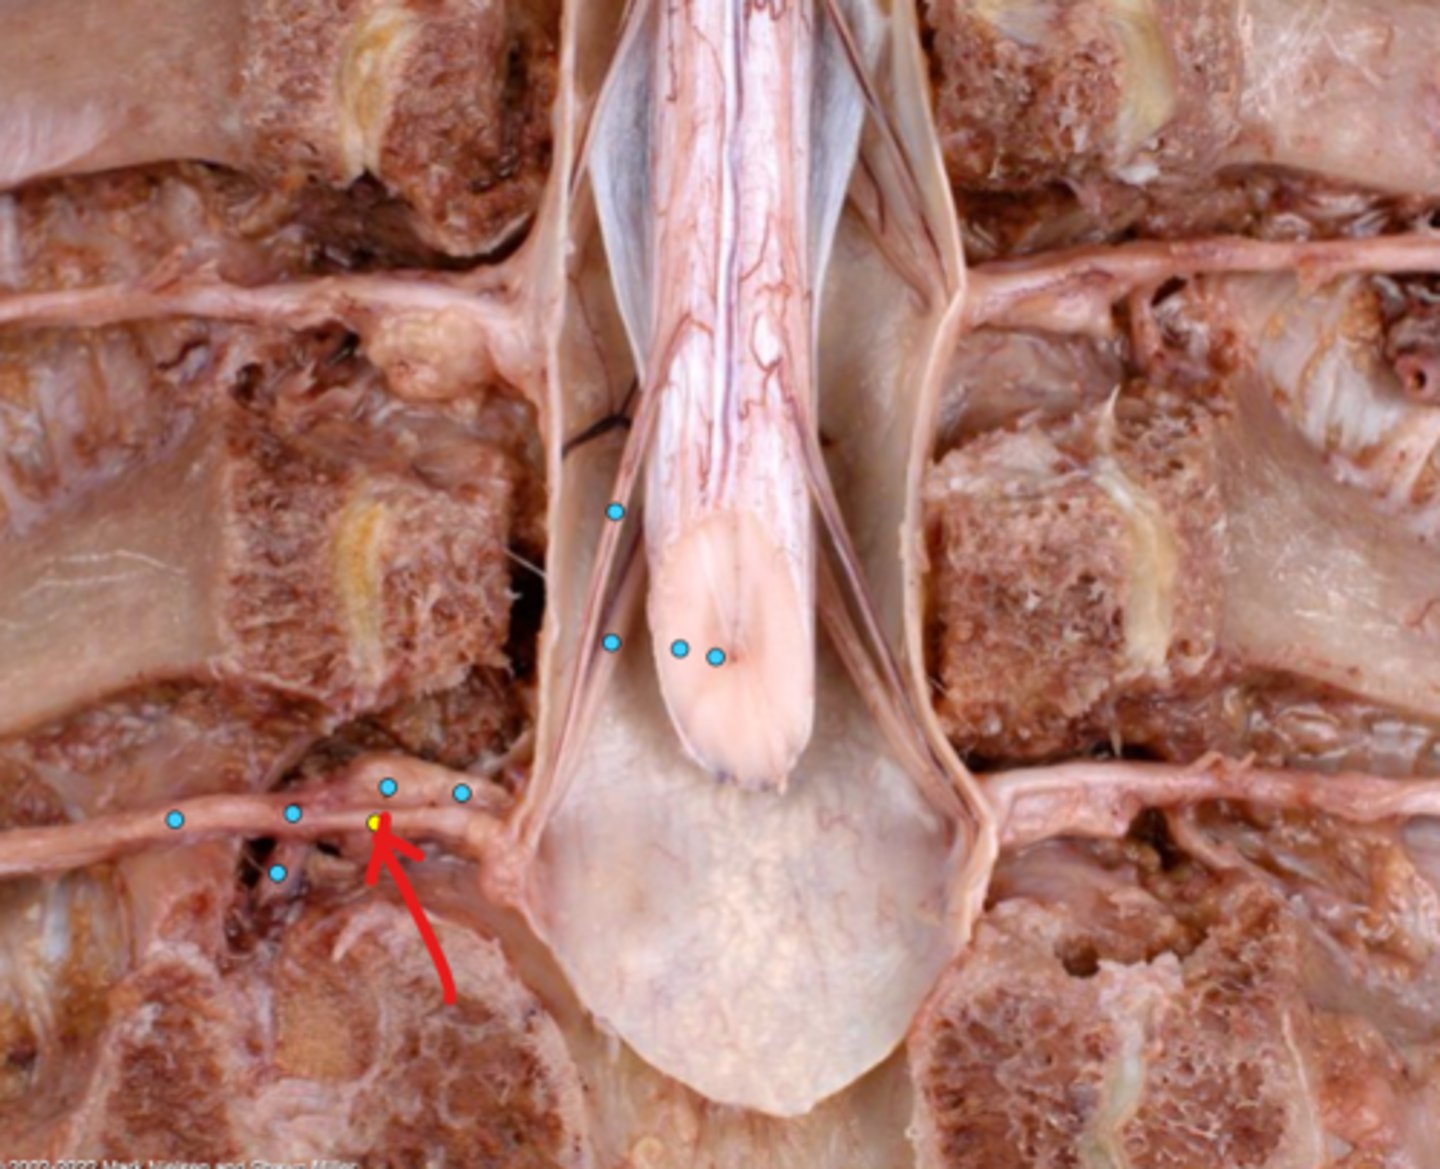

Intercostal nerve

Communicating ramus

Sympathetic trunk ganglion

Sympathetic trunk

Lesser splanchnic nerves

Greater splanchnic nerve

Anterior (ventral) ramus

Spinal nerve trunk

Posterior (dorsal) ramus

Spinal ganglion

Anterior (ventral) root

Posterior (dorsal) root

Anterior (ventral) rootlets

Posterior (dorsal) rootlets

White matter

Gray matter

Posterior (dorsal) rootlets

Anterior (ventral) rootlets

Spinal cord